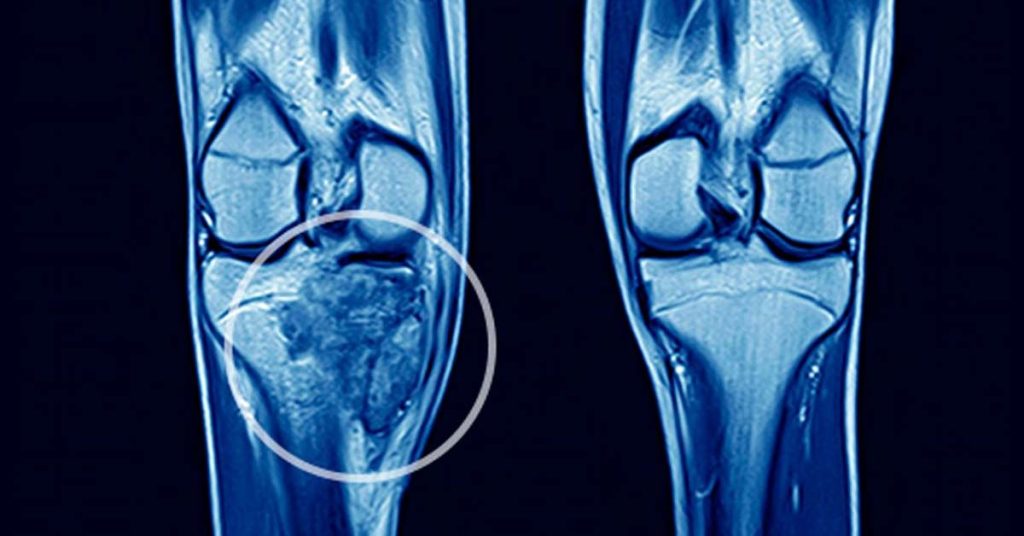

A investigação geralmente começa com exames de imagem, como radiografia, tomografia ou ressonância magnética. Quando existe suspeita de tumor, pode ser necessária uma biópsia para confirmação do diagnóstico.

Entre os tumores malignos primários do osso mais conhecidos estão o osteossarcoma e o sarcoma de Ewing, que tendem a surgir principalmente durante o período de crescimento acelerado, na adolescência.